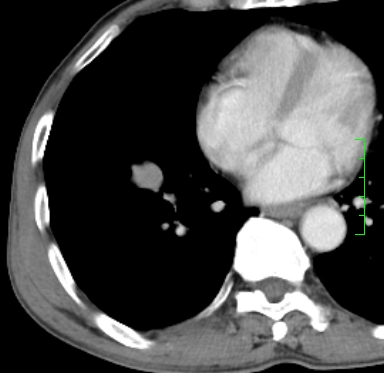

m,73y。膝关节疼痛伴双下肢水肿。入院常规胸片发现结节灶。增强为静脉期。

指套征,强化明显,近侧肺组织局限性肺气肿,考虑支气管类癌,慢支、肺气肿、双上陈旧性tb、冠脉钙化。

鉴别:先天性支气管闭锁,变态反应性支气管肺曲霉菌病,肺癌,支气管囊肿,支扩黏液嵌塞。

1)考虑右肺下叶周围型肺癌。2)右肺上叶及左肺感染性病变(结核可能)。3)肺气肿。4)冠状动脉钙化。